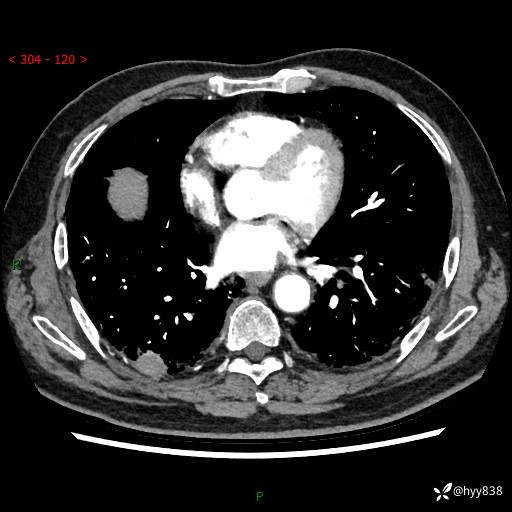

71岁/男,咳嗽伴气促半月。一年前肺手术史,又见两个结节,穿刺结果意外---结果公布~

【患者信息】:71岁/男

【主诉】:咳嗽、咳痰伴气促半月

【现病史】:患者半月前无明显诱因出现咳嗽、咳痰,为白色粘痰,无明显加重与缓解因素,伴气促,无发热,无大量脓痰,无胸痛、咯血,无哮鸣音,到我院就诊,胸部CT示右肺结节增大,并口服药物治疗无明显好转,具体用药不详,为求进一步治疗随来我院,经门诊以“孤立性肺结节”收入我科。 病程中患者精神、饮食可,睡眠不佳,大小便正常,体力下降,体重未见明显下降。

[既往史]:2022-06于当地第一人民医院确诊慢阻肺,现规律使用杰润(1次/日);2023-04-06于当地市第一人民医院行胸腔镜右肺上叶楔形切除术+右肺上叶切除术+淋巴结清扫术+胸膜黏连松解术,确诊为右肺鳞癌 pT2aN0M0 Ib期

【检查】:胸部CT平扫+增强